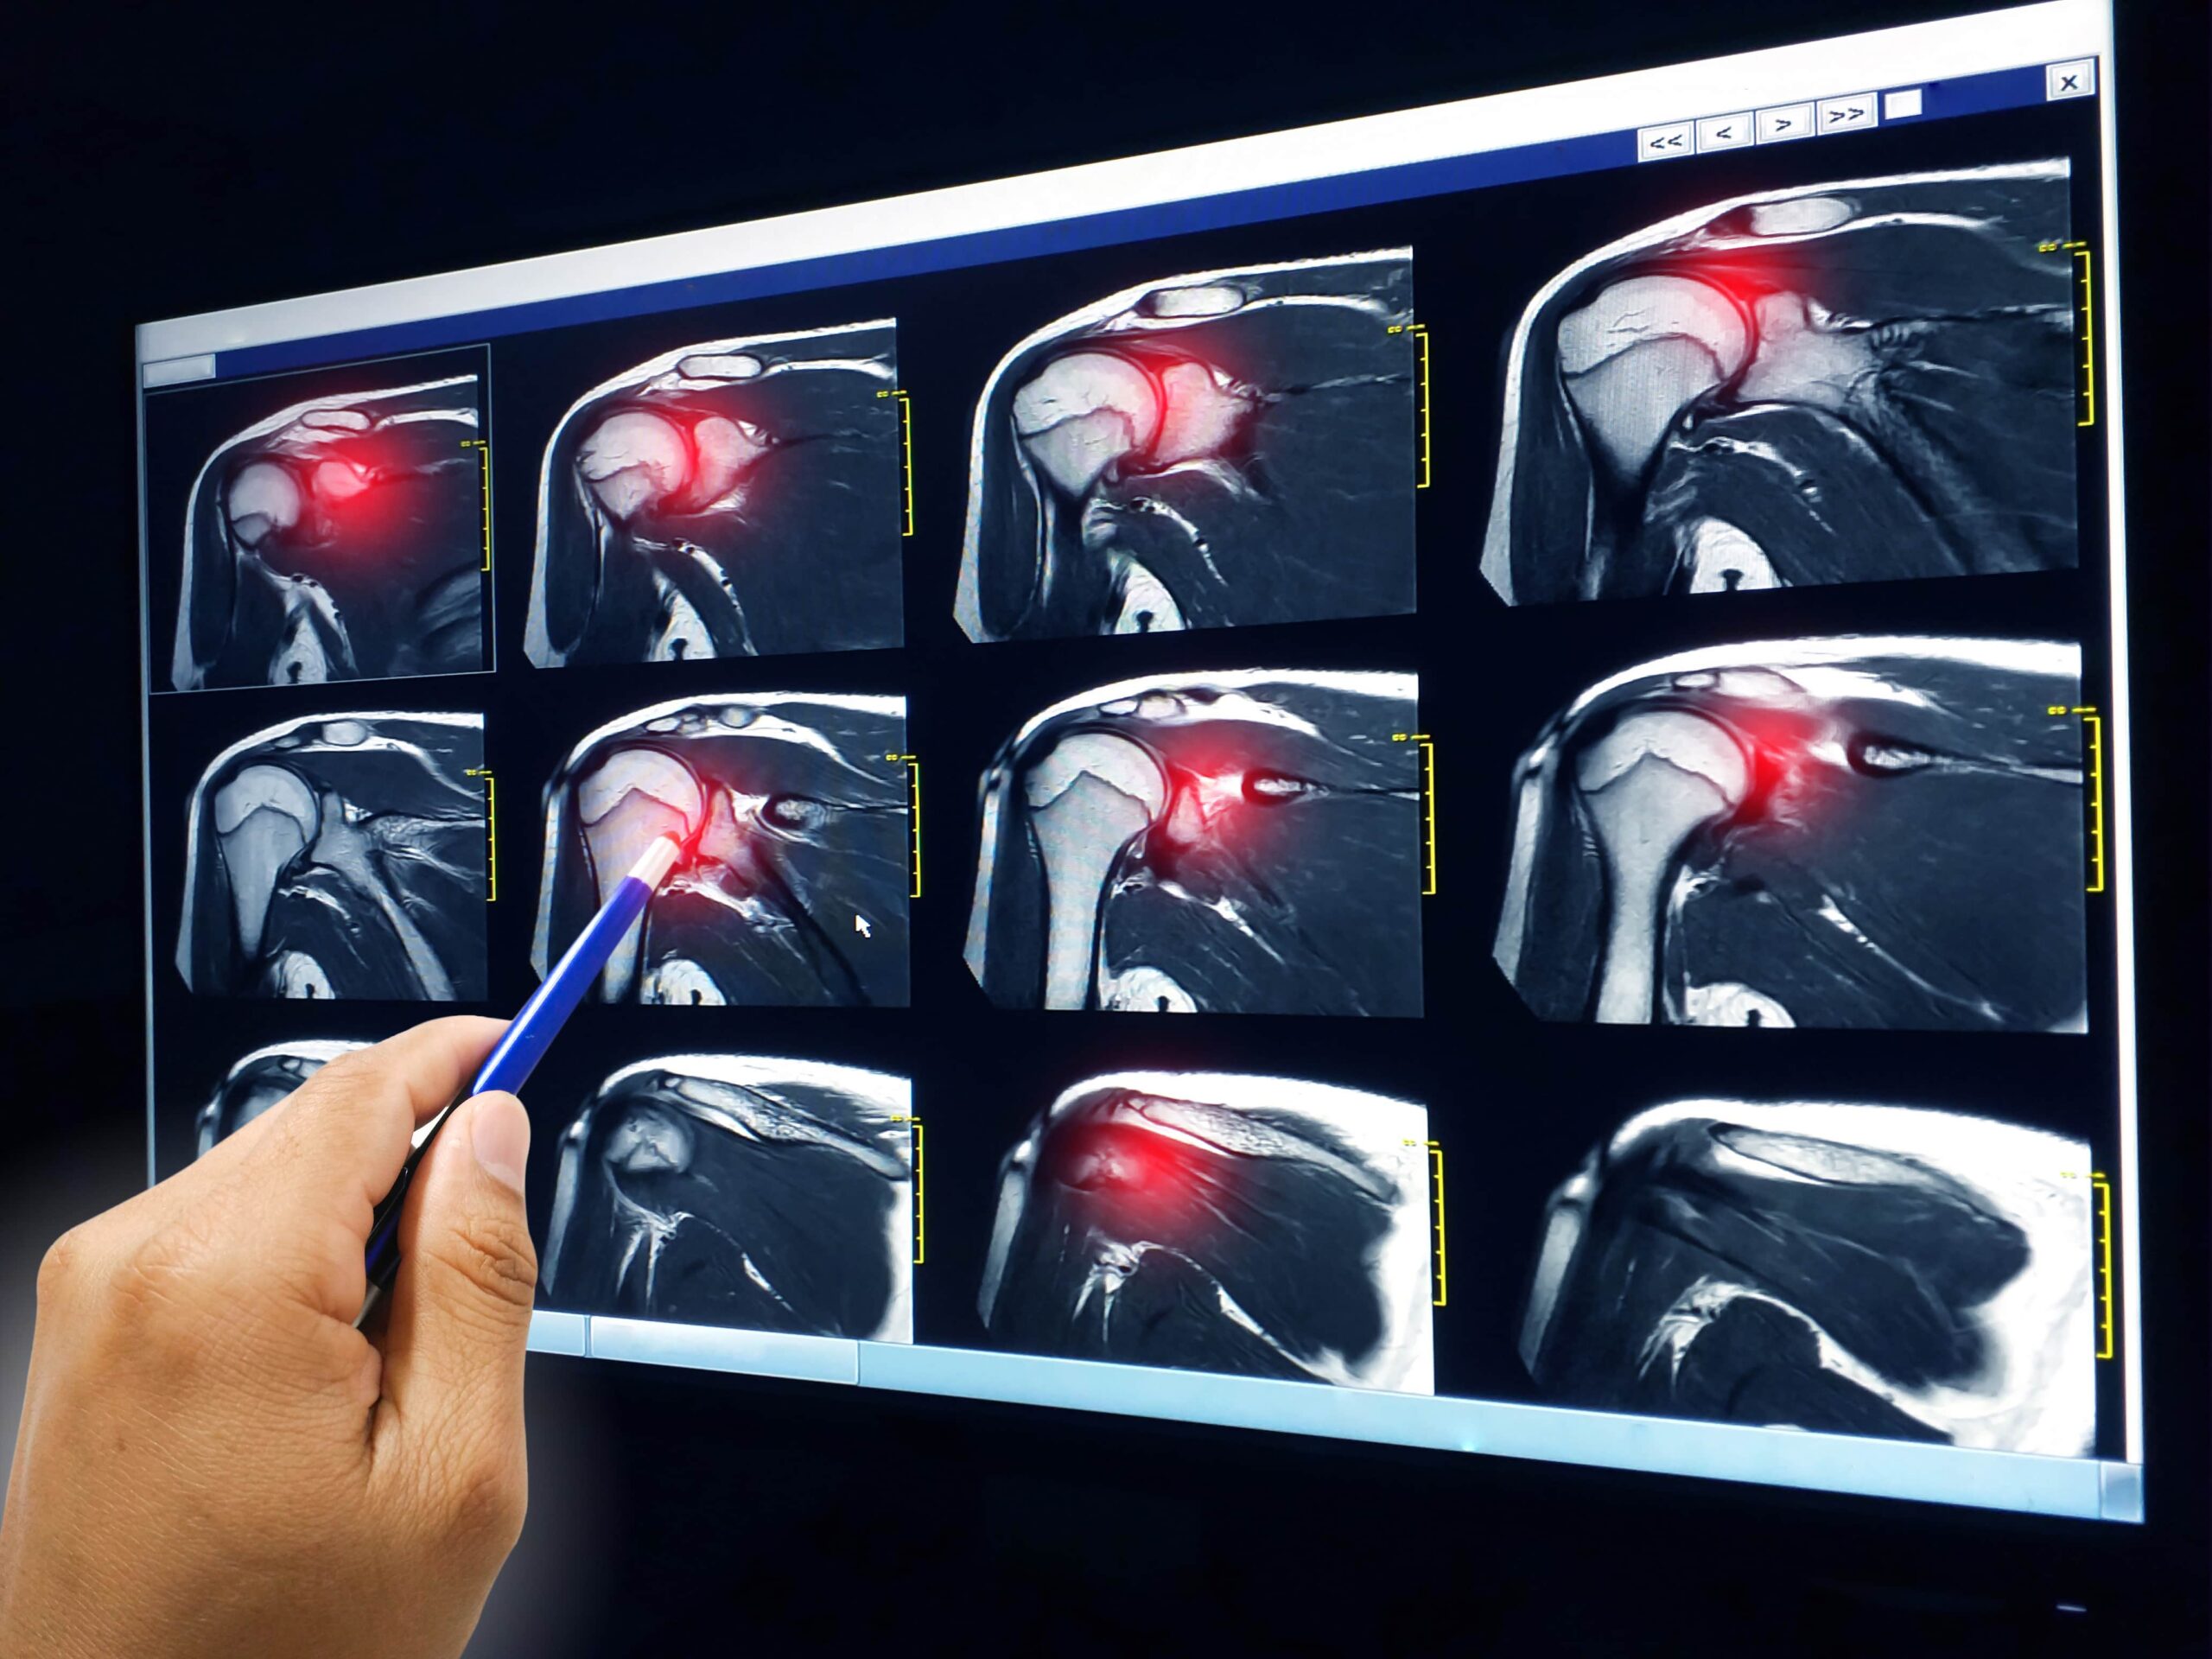

So when you first have an injury see a doctor for an initial assessment. Then, make a rehabilitation plan. Depending on the type and grade of injury, your rehab plan is drafted.

Shoulder rotator cuff injuries take a long time to heal. They are common since repetitive moves can stretch out the muscles, tendons, and ligaments. The injuries can worsen without you even being aware of them. They are preventable with the right prep work in the gym.